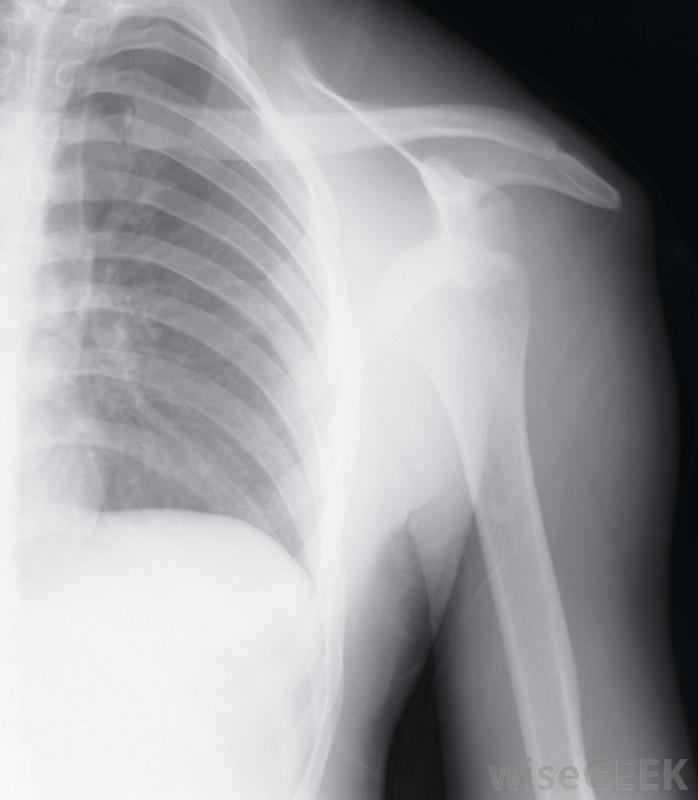

肩峰成形術是一種外科手術,治療因撞擊綜合征引起的肩部疼痛和虛弱。肌腱穿過肩胛骨頂部的肩峰骨下方,如果這些肌腱受傷或發炎,他們可以摩擦肩峰下側。肩峰成形術的目的是平滑或去除肩峰的任何粗糙部分,以便為肌腱創造更多的活動空間。在進行肩峰成形術之前,外科醫生可能需要做X光透視來觀察肩關節的骨骼。運動員如果參加包括手臂和肩部頭頂運動的體育活動,可能會患上撞擊綜合征如果肩關節疼痛,尤其是肩關節過度疼痛時,醫生也可以用這種藥物來緩解如果患者出現持續性肩痛,他的外科醫生可能想做一個肩峰成形術,他可能會先安排一系列的x光片來觀察肩關節的骨骼。其他的檢查,如核磁共振成像(MRI),也可能會被要求提供肩部有液體如果外科醫生認為肩峰成形術對患者有利,則可將其作為開放手術或關節鏡手術進行。如果冰敷和休息不能治療肩關節疼痛,肩峰成形術可能是必要的。開放性肩峰成形術是在肩前部切開一個切口,以使肌腱和肌肉都能看到。外科醫生可以切除肩峰骨的前部把骨頭下面的脊線剃掉,使其表面光滑。然后在切口打開時評估活動范圍。這種開放式手術可能需要更長的恢復時間,但它使外科醫生有更多的機會接觸肩部區域醫生可能會建議對肩關節疼痛和虛弱的患者進行肩峰成形術。肩峰成形術也可以作為一種關節鏡手術進行,其中一些在肩關節區域進行切口。插入關節鏡(包含攝像機和光源)以查看肩峰和肩關節。還插入手術器械來刮除或移除部分肩峰。這種關節鏡手術創傷小,恢復時間短在肩峰成形術后,病人應該在醫院呆上幾個小時到一個晚上。可能會有疼痛和腫脹,可以用冰和止痛藥治療。外科醫生也可以在手術后一兩天開始進行物理治療練習。通常情況下,對患者來說遵循外科醫生和理療師的建議,以使肩關節完全恢復活動范圍。開放性肩峰成形術比關節鏡手術更具侵入性。